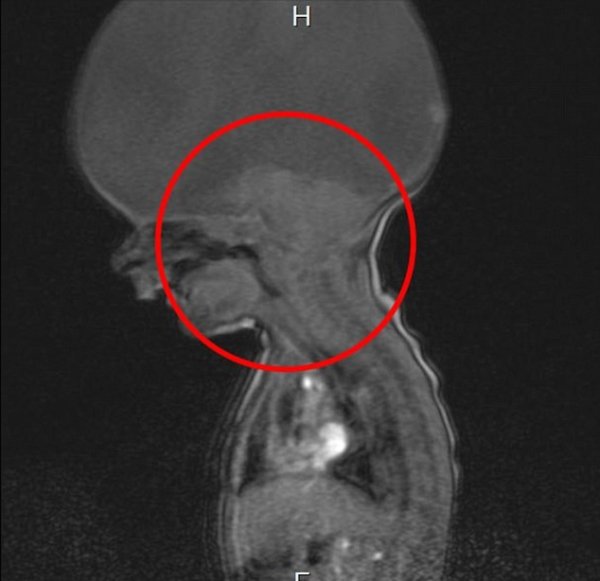

Holoprosencefalija, rijetka bolest koja uzrokuje prestanak razvitka mozga tokom razvoja bebe u stomaku. Rendgenski i drugi snimci pokazivali su da se bebin mozak neće razvijati u skladu s vremenom.

Samo je moždano stablo bilo razvijeno, što je značilo da može da reguliše disanje i ostale fiziološke funkcije. Praznina u dječakovoj glavi bila je ispunjena tečnostima.